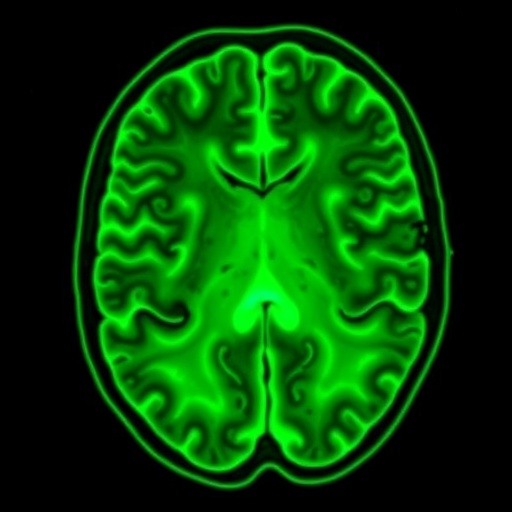

The design of the MOMENTUM-1 trial incorporates sophisticated imaging and biomarker analyses to monitor treatment response and disease progression meticulously. Advanced MRI techniques and somatostatin receptor PET imaging are employed periodically to assess tumor burden and radiotracer uptake, facilitating personalized treatment adjustments. Moreover, translational research components integrated within the trial aim to elucidate molecular determinants of response and resistance, potentially identifying predictive biomarkers and novel combination strategies.